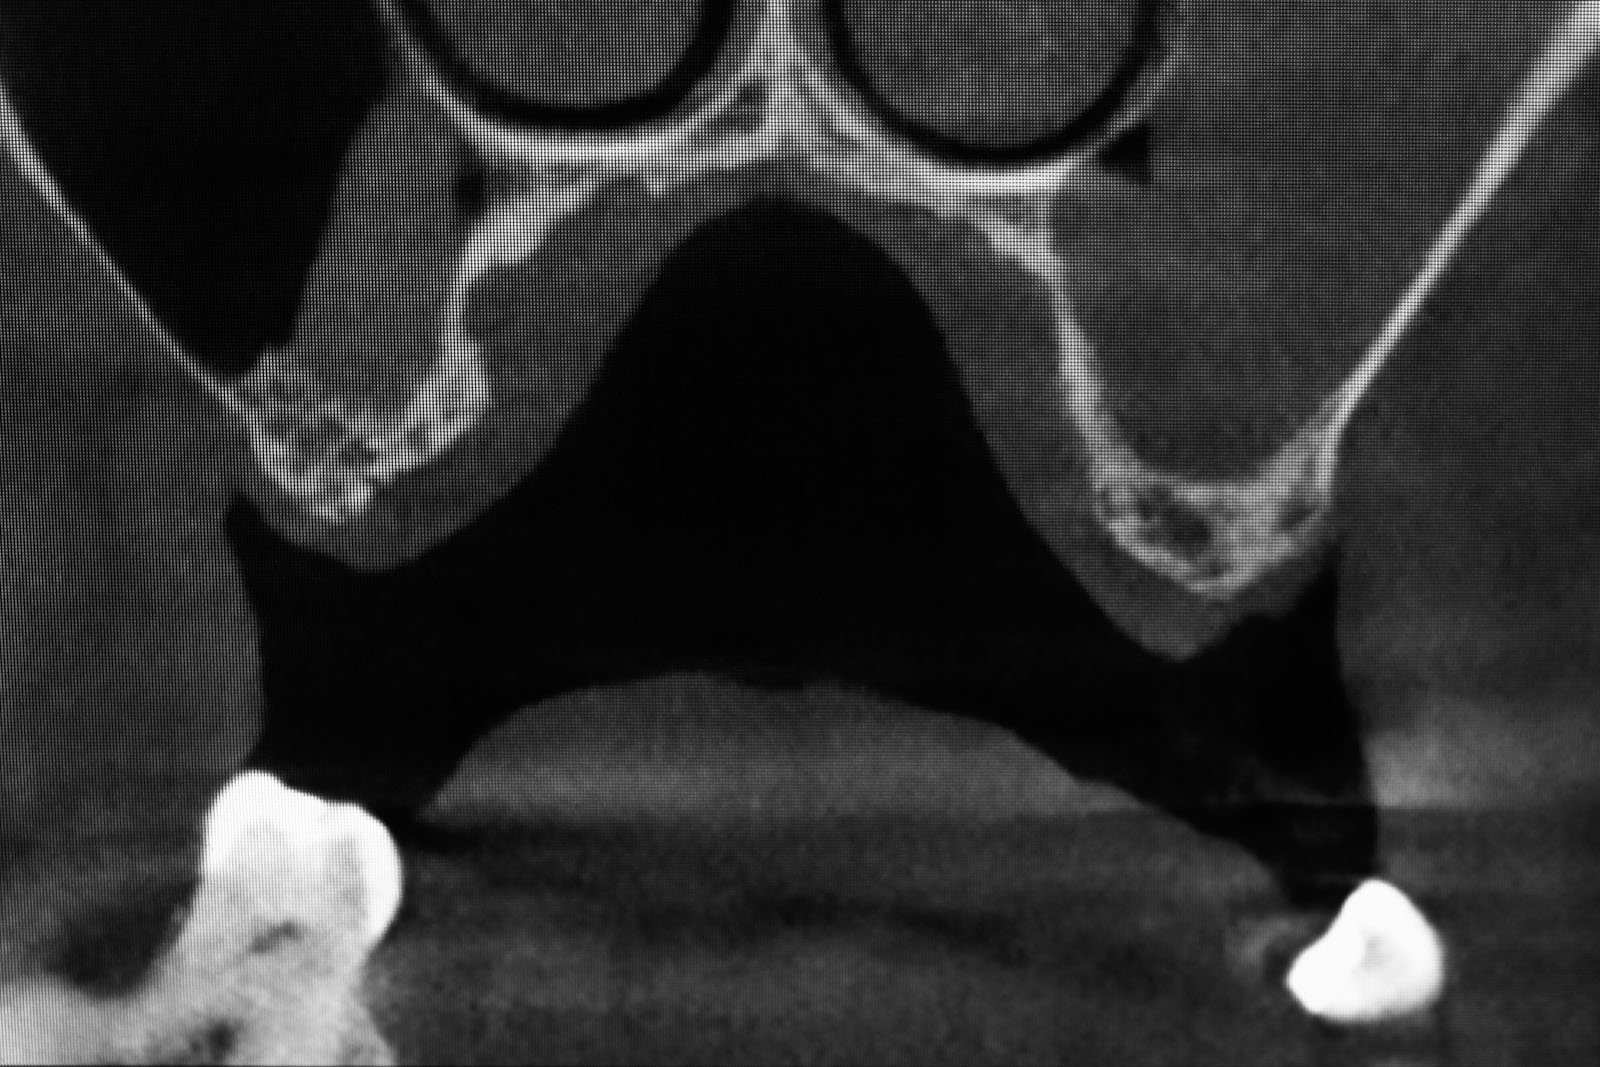

Tomografia komputerowa szczęk CT – ocenia stan i czystość zatok szczękowych, stopień skrzywienia przegrody nosa, drożność otworu zatoki szczękowej oraz anatomię tzw. zespołu ujściowo-przewodowego, od którego zależy długoterminowy efekt leczenia, kształt i wymiary kości jarzmowej.

Tomografia komputerowa stożkowa CBCT – ocenia wszystkie powyższe parametry anatomiczne, które przedstawia na trójwymiarowym obrazie.

CBCT, które wybiórczo może okazać stan kości w pozostałej części zębodołowej szczęk, stan oraz powietrzność zatok szczękowych, co jest istotnym parametrem kwalifikującym pacjenta do zabiegu operacyjnego, stan przegrody nosa

CT tomografia komputerowa liniowa ukazująca stan całości zatok okołonosowych, drzewo małżowinowe, stopień skrzywienia przegrody nosa, stopień obturacji naturalnego otworu łączącego jamę nosa z zatoką szczękową – rozworu zatoki szczękowej.